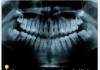

U današnjem članku vam pišemo na temu kako možete efikasno ukloniti zubni kamenac koristeći prirodne sastojke koje sigurno već imate kod kuće. Saznajte...

Problem kamenca...